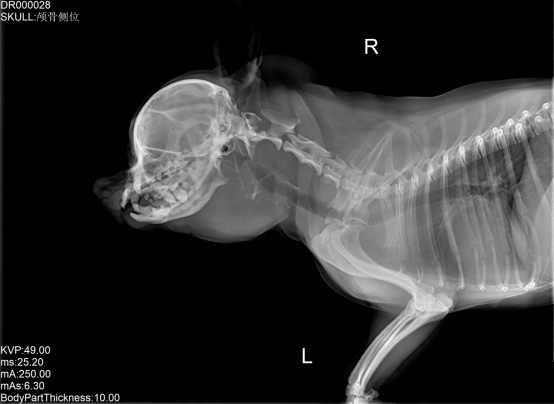

寵物DR是專業(yè)用于寵物X光拍攝的數(shù)字化X射線檢查,輔助寵物醫(yī)生進(jìn)行及時(shí)精確的診療。寵物DR主要包括五大主要部件,數(shù)字X光探測(cè)器,高壓發(fā)生器,球管,機(jī)架,寵物專用的DR工作站軟件。寵物DR由于采用數(shù)字技術(shù),自動(dòng)成像處理,模擬X線圖像向數(shù)字化X線圖像的轉(zhuǎn)變。寵物DR與傳統(tǒng)模擬X光機(jī)相比有什么優(yōu)勢(shì)呢?采集時(shí)間10毫秒以下,成像時(shí)間僅為3秒,較高的空間分辨力和低噪聲率,提高了病灶的檢出率,避免漏診誤診等問(wèn)題。減少X線對(duì)人體照射的不良影響寵物DR照片是您最佳的選擇。提高寵物醫(yī)生工作效率,總而言之,選擇寵物DR是寵物醫(yī)院的最佳選擇。寵物醫(yī)學(xué)影像學(xué)實(shí)現(xiàn)全數(shù)字化和無(wú)膠片化升級(jí)發(fā)展提高技術(shù)水平。